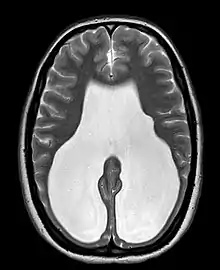

Colpocephaly is a cephalic disorder involving the disproportionate enlargement of the occipital horns of the lateral ventricles and is usually diagnosed early after birth due to seizures. It is a nonspecific finding and is associated with multiple neurological syndromes, including agenesis of the corpus callosum, Chiari malformation, lissencephaly, and microcephaly.[1] Although the exact cause of colpocephaly is not known yet, it is commonly believed to occur as a result of neuronal migration disorders during early brain development, intrauterine disturbances, perinatal injuries, and other central nervous system disorders.[2] Individuals with colpocephaly have various degrees of motor disabilities, visual defects, spasticity, and moderate to severe intellectual disability.[3] No specific treatment for colpocephaly exists, but patients may undergo certain treatments to improve their motor function or intellectual disability.

Colpocephaly is characterized by disproportionately large occipital horns of the lateral ventricles (also frontal and temporal ventricles in some cases). MRI and CT scans of patients demonstrate abnormally thick gray matter with thin poorly myelinated white matter. This happens as a result of partial or complete absence of the corpus callosum. Corpus callosum is the band of white matter connecting the two cerebral hemispheres. The corpus callosum plays an extremely important role in interhemispheric communication, thus lack of or absence of these neural fibers results in a number of disabilities.[12]

After birth, MR imaging can be done to look for cephalic abnormalities. This is the most commonly used method for diagnosing colpocephaly. Physicians look for abnormally large occipital horns of the lateral ventricles and diminished thickness of white matter.[12] Spinal tapping is not a preferred method for diagnosis because newborn babies with colpocephaly or hydrocephaly have open fontanelles which makes it difficult to collect CSF. Also, colpocephaly is not associated with increased pressure.[13]